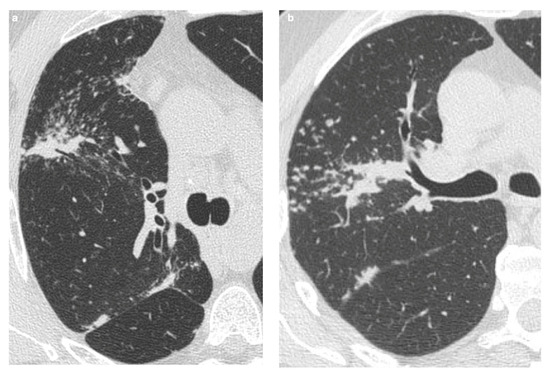

The Role of High-Resolution Lung Computed Tomography to Distinguish Between Fibrosing Hypersensitivity Pneumonitis and Usual Interstitial Pneumonia

by Dmitry A. Kuleshov, Svetlana Yu. Chikina, Galina V. Nekludova, Igor E. Tyurin and Sergey N. Avdeev

Background: Hypersensitivity pneumonitis (HP) is an interstitial lung disease (ILD) caused by repeated exposure to inhaled antigens in susceptible subjects. High-resolution computed tomography (HRCT) of the lungs is the leading diagnostic method for ILDs, but in some cases HRCT findings are not sufficient to distinguish HP and other ILDs, particularly, fibrotic HP (fHP) and usual interstitial pneumonia (UIP). Objective: The aim of this study was to develop HRCT criteria to diagnose fHP in patients with a UIP-like pattern. Methods: In this retrospective study, we analyzed HRCT scans of patients with fHP and a UIP-like pattern who underwent lung biopsy, and patients with idiopathic pulmonary fibrosis (IPF) and a UIP pattern in HRCT. Results: We included 51 patients with confirmed fHP and 24 patients with IPF/UIP in the analysis. IPF/UIP patients were older, were prevalently males, and did not have any systemic autoimmune diseases or risk factors for other ILDs. fHP patients were younger, with an equal number of males and females, and were more likely to be exposed to environmental antigens. HRCT abnormalities in the fHP group predominated in the lower lung areas or were diffuse in axial scans, whereas IPF/UIP patients mostly demonstrated a diffuse craniocaudal distribution and subpleural axial predominance. Centrilobular nodules and mosaic attenuation were present significantly more often in the fHP group; honeycombing, traction bronchiectasis, and emphysema prevailed in IPF/UIP patients. In the logistic regression analysis, patients with fHP and IPF/UIP differed in the presence of centrilobular nodules, honeycombing, and in both craniocaudal and axial distributions of HRCT abnormalities. In the ROC analysis, the combination of centrilobular nodules, honeycombing, and diffuse axial and craniocaudal distributions can predict the diagnosis of fHP (AUC, 0.953 ± 0.022; 95%CI, 0.910–0.995; p < 0.001). Mosaic attenuation and reticulation did not change the probability of fHP. Conclusions: The most significant HRCT features of fHP compared to the UIP pattern were centrilobular nodules, honeycombing, and a diffuse axial and craniocaudal distribution of abnormal findings. Reticulation, mosaic attenuation, and GGO do not increase the probability of fHP. Full article